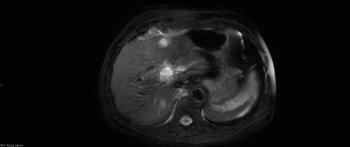

An 83-year-old man was diagnosed with multiple low-grade transitional cell carcinomas over a 6-year period. A surveillance cystoscopy in year 7 showed high-grade noninvasive papillary urothelial carcinoma in the bladder trigone. A CT urogram showed a soft-tissue mass with diffuse enhancement in the lower pole of the left kidney, concerning for malignancy.